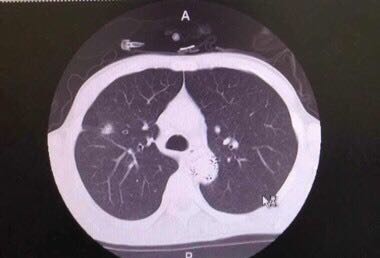

患者,男,44岁,患者无明显诱因出现吞咽困难,不伴恶心、呕吐、反酸,无胸痛、心悸、呼吸困难。增强CT发现胸主动脉处动脉瘤,检查过程中出现上消化道大出血,出血量2000ml。病情危急,立即配输血,血压90/50mmhg,时间紧急,无全麻状态下实施胸主动脉瘤腔内修复术(DSA),后经胃镜证实,为胸主动脉瘤破入食管,穿透性溃疡。术后患者血压回升,转入ICU,病情稳定。